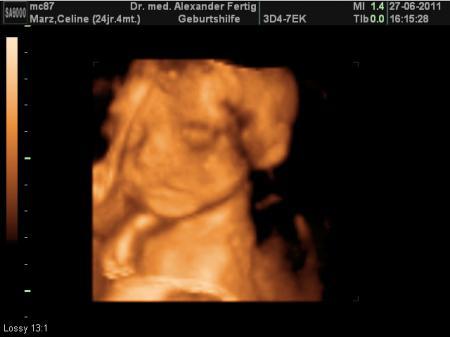

Hallöchen meine runden Kugeln , hatte heute wieder einen Termin bei meinem Gyn. alles supi...Baby hat kräftig zugenommen! Wiegt nun 625g, liegt genau im Normalbereich, lt. meines Arztes. Ach wie süss... die kleine Maus musste während der Schallung 2x gähnen . Hat sogar 1x gelächelt sieht man alles auf den Videos, die man hier leider nicht hochladen kann . Ach, ich hab jetzt übrigens auch ne Fledermaus...das darf Sie bis zur Geburt auch gern bleiben. In 3 Wochen lass ich dann den Zuckertest machen.

Das sind ja tolle Neuigkeiten. Dein Baby ist ja seehr süß Ich finde es immer wieder erstaunlich, wie gut man auf diesen Bildern die kleinen Gesichtchen sieht :-) Ich darf morgen wieder hin, und hoffentlich habe ich dann auch so einen tollen Blick. Beim letzten Mal hatte die Kleine Nabelschnur und Hände vorm Gesicht und man konnte gar nichts sehen. Liebe Grüße

danke schön anfangs fand ich 3d etwas unheimlich aber je mehr sie zunimmt desto schöner werden die bilder. lässt du auch 3d ultraschall machen?

ja genau, mein arzt macht immer zuerst "normale" beschallung um nach dem rechten zu sehen wie oberschenkellänge, bauchumfang, kopfumfang...alles was er so wissen möchte und dann schaltet er in den 3d modus, dass ich auch was von der schallung hab :-P ich hab einmalig 60€ gezahlt und bekomm alle bilder und videos auf ne cd jedesmal gebrannt.